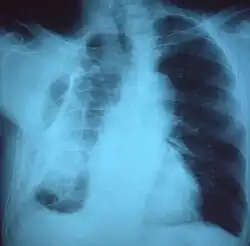

A fibrothorax can typically be diagnosed by taking an appropriate medical history in combination with the use of appropriate imaging techniques such as a plain chest X-ray or CT scan.[3] These imaging techniques can detect fibrothorax and pleural thickening that surround the lungs.[7] The presence of a thickened peel with or without calcification are common features of fibrothorax when imaged.[3] CT scans can more readily differentiate whether pleural thickening is due to extra fat deposition or true pleural thickening than X-rays.[3]

If a fibrothorax is severe, the thickening may restrict the lung on the affected side causing a loss of lung volume.[7] Additionally, the mediastinum may be physically shifted toward the affected side.[3] A reduction in the size of one side of the chest (hemithorax) on an X-ray or CT scan of the chest suggests chronic scarring.[6] Signs of the underlying disease causing the fibrothorax are also occasionally seen on the X-ray.[6] A CT scan may show features similar to those seen on a plain X-ray.[7] Lung function testing typically demonstrates findings consistent with restrictive lung disease.[6]